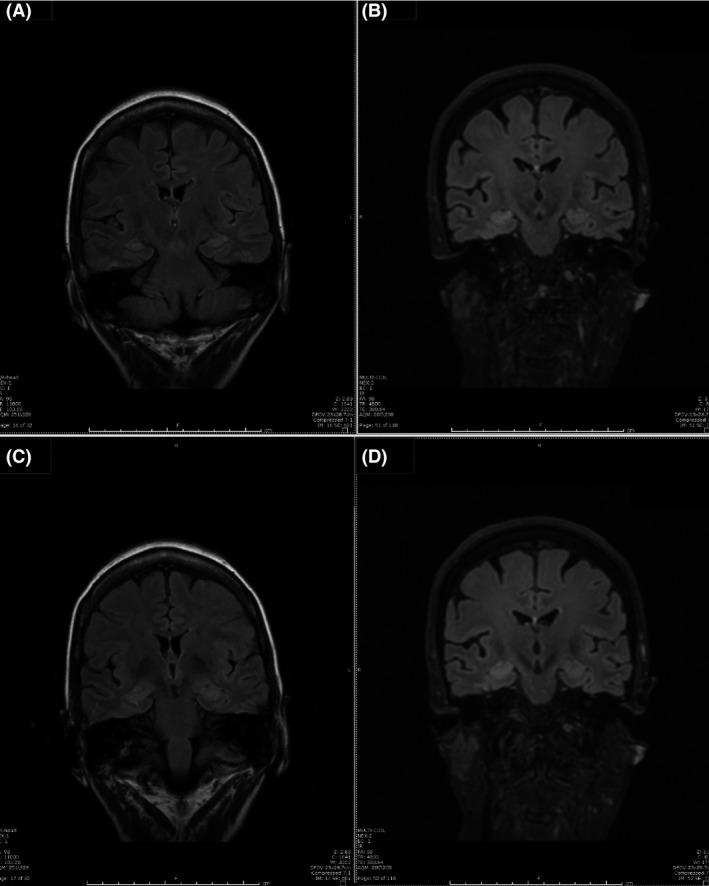

Reversible dementia: subclinical seizure in early-onset dementia.

We report a case of early-onset dementia with subclinical seizures. Aggressive seizure control improved the patient's cognition. Commonly, an EEG is only performed following overt behavioral seizures. Therefore, subclinical seizures tend to be underdiagnosed. Serial or extended EEG should be seriously considered in patients with early-onset dementia.

我们报告一例伴有亚临床发作的早发性痴呆病例。积极控制癫痫发作改善了患者的认知。通常,脑电图仅在出现明显的行为性癫痫发作后才进行。因此,亚临床发作往往诊断不足。对于早发性痴呆患者,应认真考虑进行连续或延长脑电图检查。